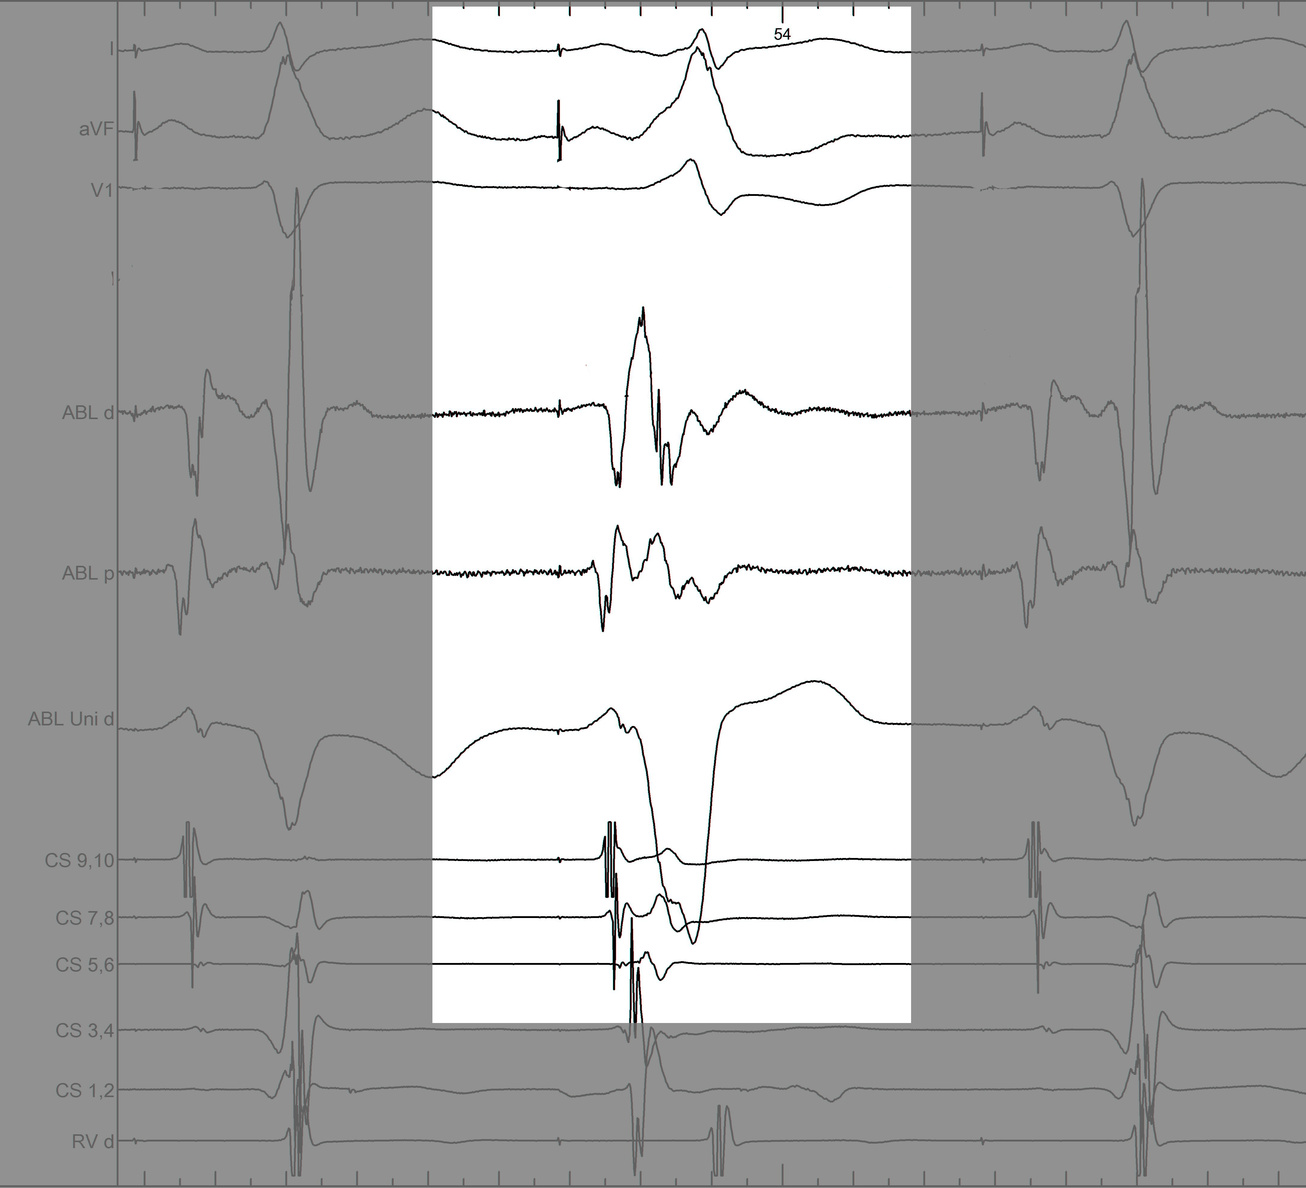

Earliest A or Potential ?

pot_late_a.jpg

The “isolated AP potential” identifies the middle of the AP and is the ideal target for ablation

Warren Jackman

Accessory pathway recording and ablation. Heart Rhythm, Vol 18, No 5, May 2021;834, https://doi.org/10.1016/j.hrthm.2021.01.008